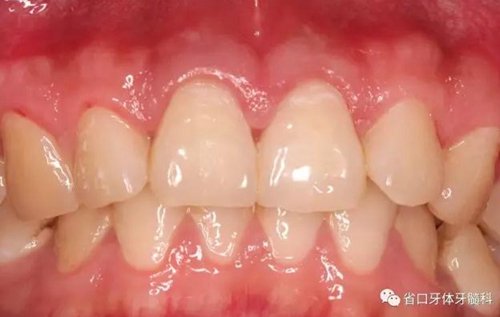

圖1:術(shù)前口內(nèi)照

檢查:11、21牙體組織完整,冷熱刺激無(wú)明顯疼痛不適,叩診+,松-,牙齦無(wú)紅腫,探診深度2-3mm,電活力測(cè)試同正常對(duì)照牙,數(shù)值為5,正常對(duì)照牙為4;